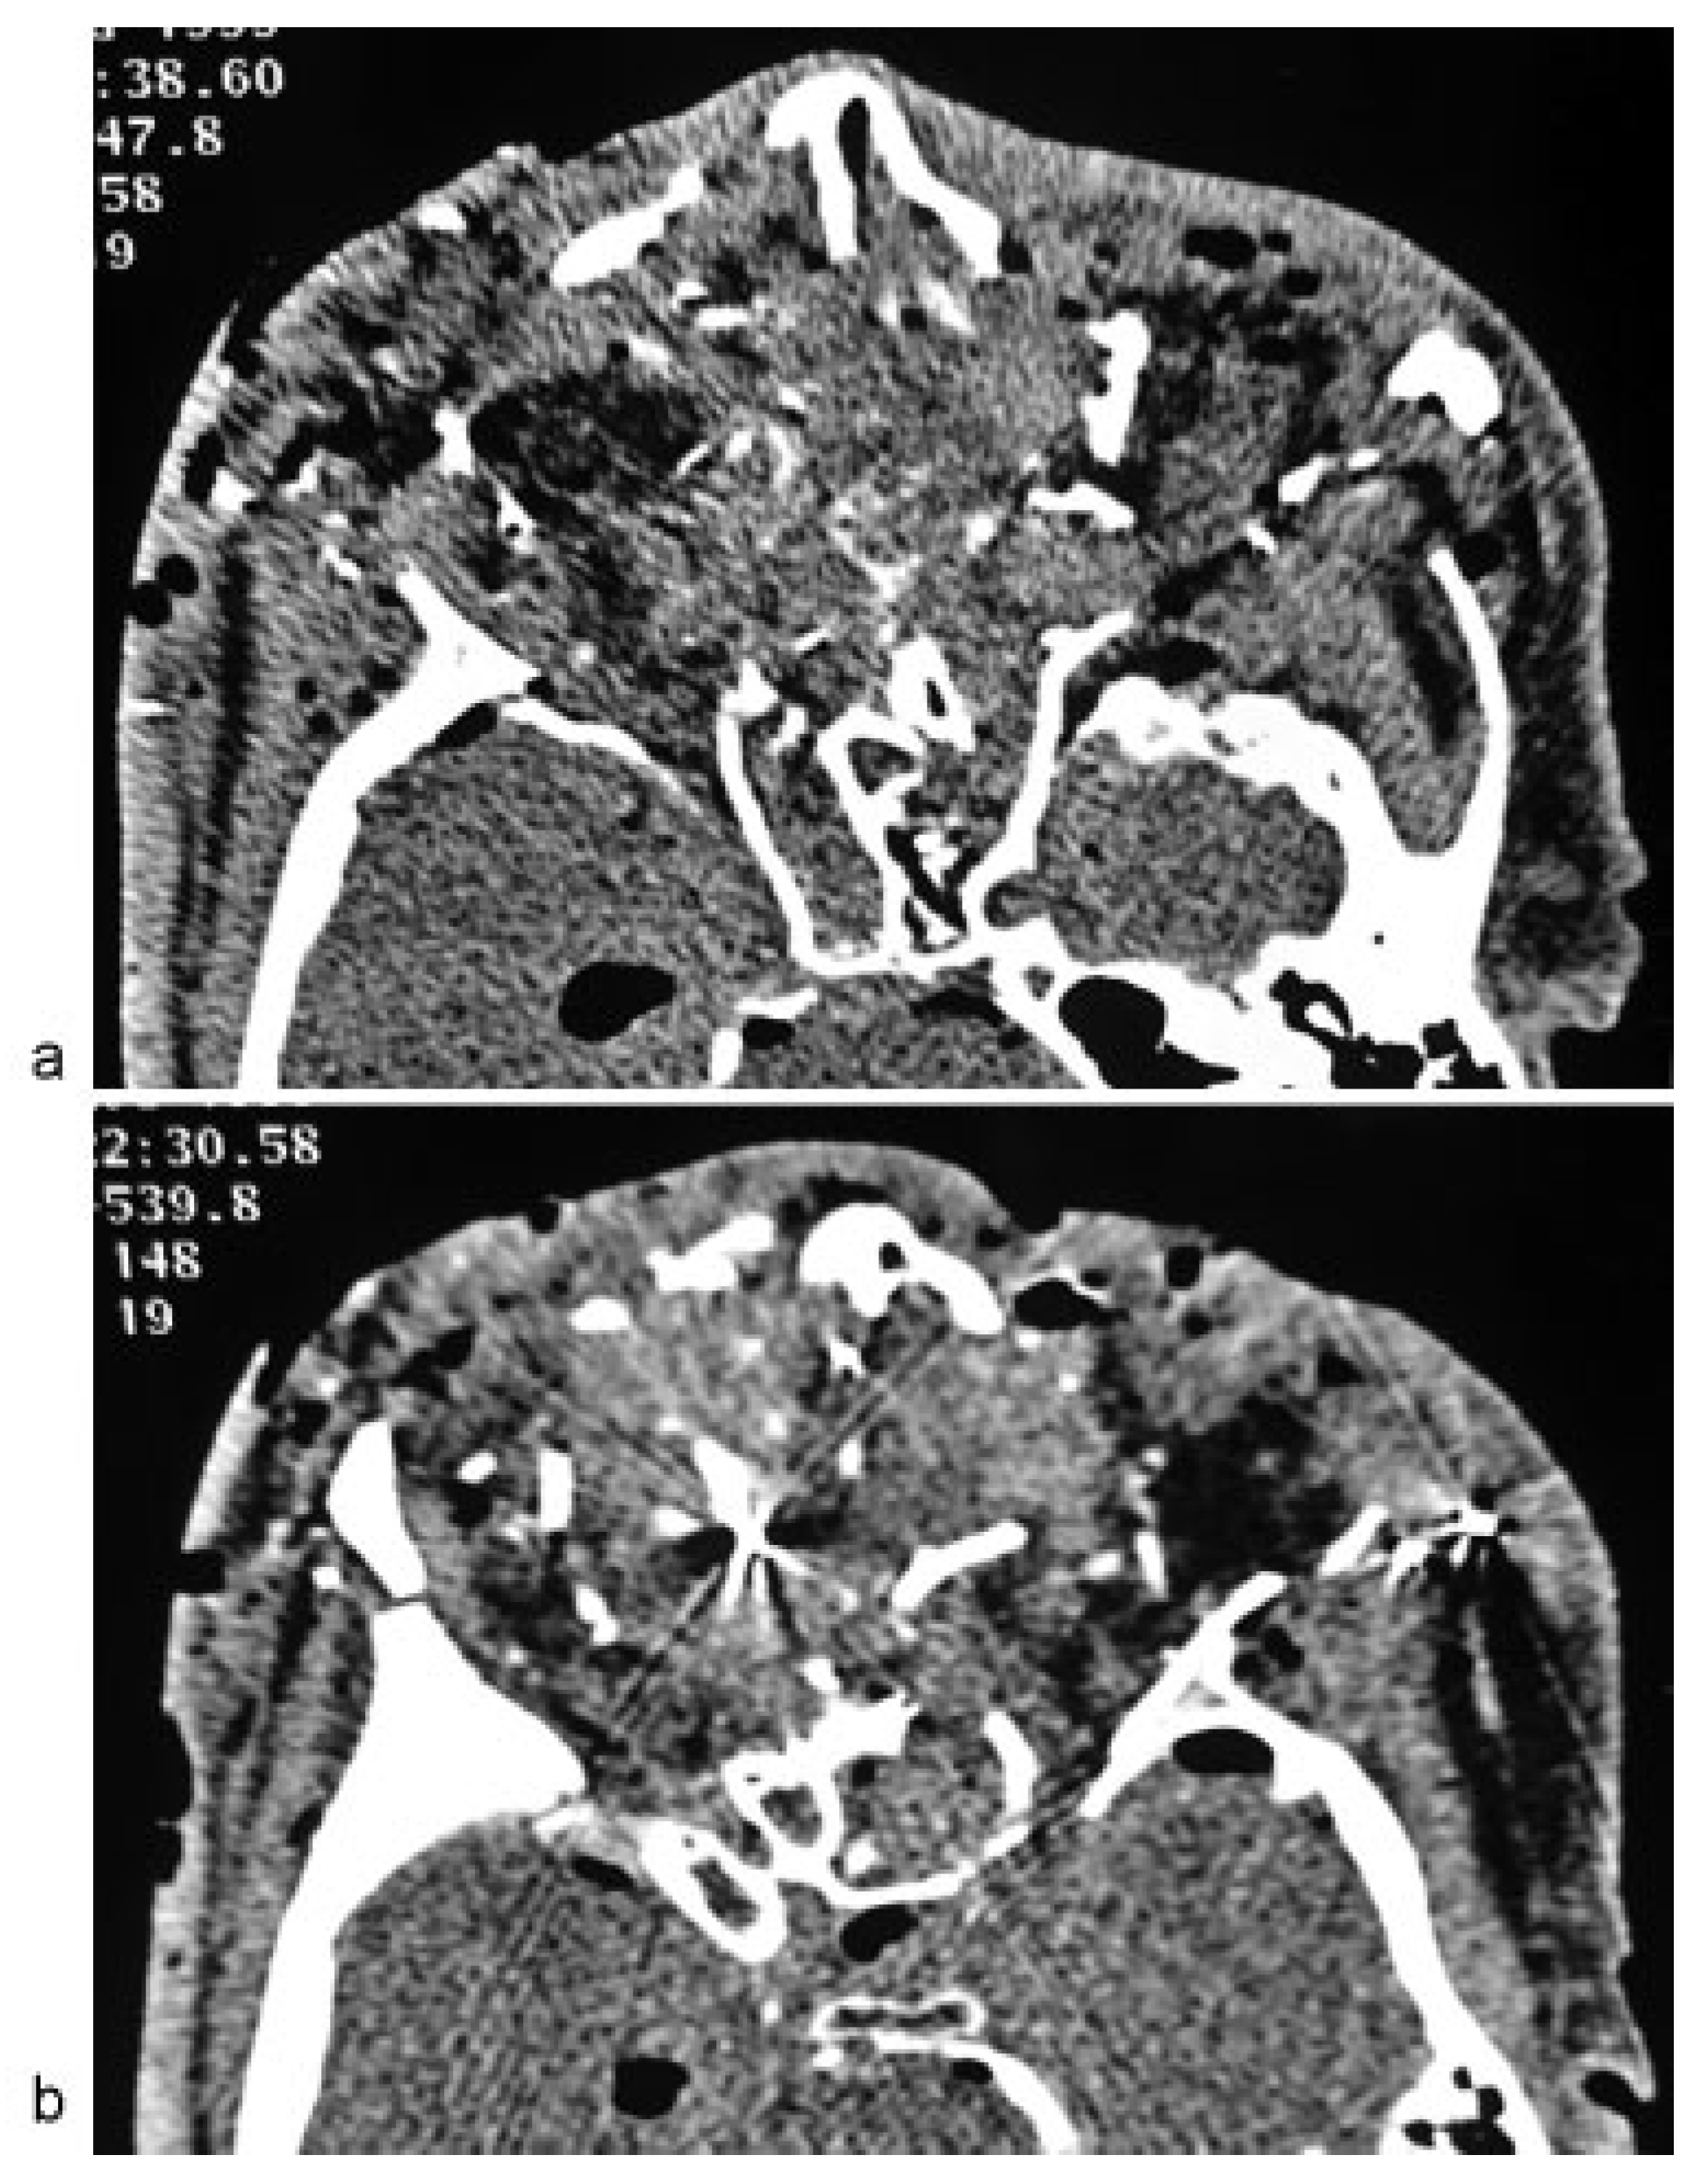

• Case 5: A dramatic case of a shooting was presented by a 50-year-old patient, who was found in his apartment with severe injuries to his midface. The patient had attempted to commit suicide by positioning a gun to his right temple. Due to excessive bleeding and insufficient respiration, the patient was intubated and transferred to the hospital. At the time of arrival, the patient presented unstable blood circulation with hypotension, which was treated by intensive blood transfer and transfusion management with the administration of catecholamines. A cranial MDCT scan confirmed the severe injuries of the patient, which included extensive destruction of the midface including the orbits and ocular bulb, in addition to the presence of multiple projectile fragments and dislocated intracranial bone fragments (Figure 5a,b). Furthermore, intracranial bleeding, fracture of the skull base, and a pneumocephalus were also present. The condition of the patient subsequently deteriorated with a poor prognosis, and the patient died without any further intervention.

Figure 5. (a,b) Axial multidetector computed tomography scan revealing massive destruction with comminuted fracture of the orbital region, in addition to hyperdense foreign bodies and artifacts.